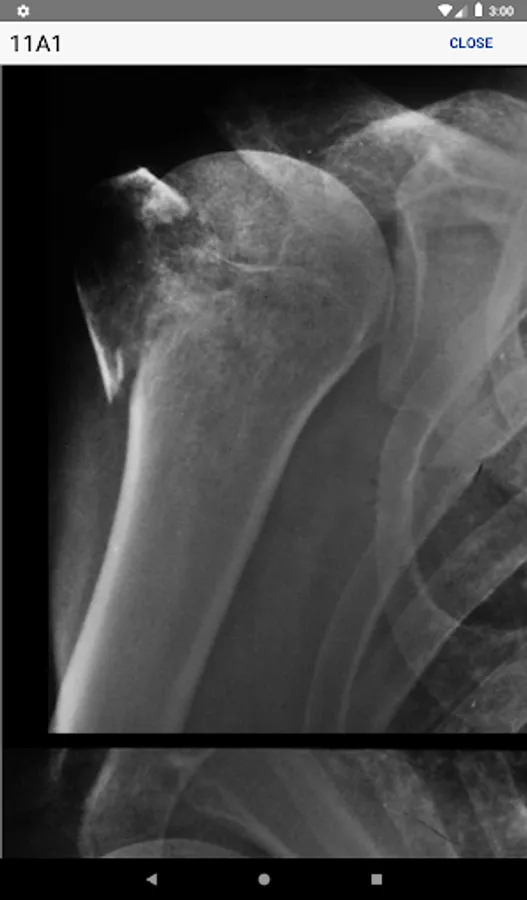

• Information regarding radiological investigations used for classifying a specific fracture

• High-quality, enlargeable x-rays are included